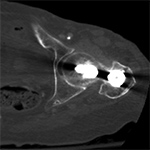

Artifact summation Artifact summation Windowing Windowing

Artifact Summation. (A) Scout image demonstrates bilateral total hip arthroplasties. (B) Axial CT image at the level of acetabular cup and femoral head shows severe transverse streaking related to total summed attenuation of metal components. Optimal Windowing. (A) Axial CT image of the pelvis viewed in soft tissue windows demonstrates extensive streak artifact due to total hip arthroplasty prohibiting evaluation of adjacent bone and soft tissue structure. (B) Same axial CT image set to bone windows results in improved visibility of adjacent bone and soft tissue anatomy.